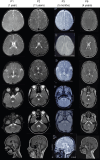

Erythrocyte membrane protein band 4.1 like 3 (EPB41L3: NM_012307.5), also known as DAL1, encodes the ubiquitously expressed, neuronally enriched 4.1B protein, part of the 4.1 superfamily of membrane-cytoskeleton adaptors. The 4.1B protein plays key roles in cell spreading, migration and cytoskeletal scaffolding that support oligodendrocyte axon adhesions essential for proper myelination. We herein describe six individuals from five unrelated families with global developmental delay, intellectual disability, seizures, hypotonia, neuroregression and delayed myelination. Exome sequencing identified biallelic variants in EPB41L3 in all affected individuals: two nonsense [c.466C>T, p.(R156*); c.2776C>T, p.(R926*)] and three frameshift [c.666delT, p.(F222Lfs*46); c.2289dupC, p.(V764Rfs*19); c.948_949delTG, p.(A317Kfs*33)]. Quantitative-real time PCR and western blot analyses of human fibroblasts harbouring EPB41L3:c.666delT, p.(F222Lfs*46) indicated ablation of EPB41L3 mRNA and 4.1B protein expression. Inhibition of the nonsense mediated decay (NMD) pathway led to an upregulation of EPB41L3:c.666delT transcripts, supporting NMD as a pathogenic mechanism. Epb41l3-deficient mouse oligodendroglia cells showed significant reduction in mRNA expression of key myelin genes, reduced branching and increased apoptosis. Our report provides the first clinical description of an autosomal recessive disorder associated with variants in EPB41L3, which we refer to as EPB41L3-associated developmental disorder (EADD). Moreover, our functional studies substantiate the pathogenicity of EPB41L3 hypothesized loss-of-function variants.